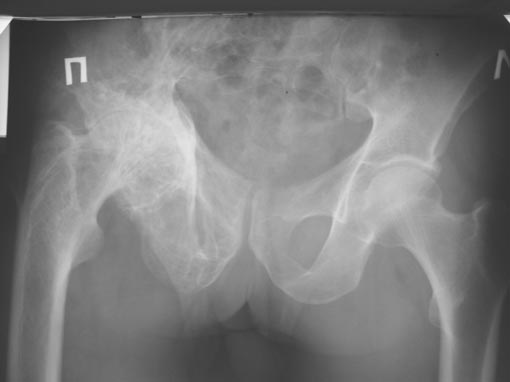

Больной 55 лет, страдает болезнью Педжета. Сформировалась грубая сгибательно-приводящая контрактура, ортопедическое укорочение 6см, движения в суставе - минимальные. Вызывает сомнение стабильность фиксации вертлужного компонента.

Мне кажется, что бесцементная чашка "пресс-фит" встанет без особых проблем и будет стабильна, возможна и установка чашки типа Цваймюллера. АИФ.

Ваши сомнения представляются обоснованными из-за качества кости. М.б. при достаточном размерном выборе получится плотная посадка полусферического компонента, но я бы имел в виду и укрепляющие опоры RRM или RCB-S и цементирование чашки.

I would treat Paget▓s as any other arthritic joint.

In my experience there is no problem using press fit cup. Make sure you have large sizes. The acetabulum is in protrusio (medialized). When you bring it out with a large cup and use femoral component with appropriate size neck you will lengthen this patient▓s leg. Concern: sciatic nerve. While traditional 2.5 cm lengthening is the maximal amount without risking much sciatic nerve (reference?), in situation like this, when shortening took place gradually, even larger amount of lengthening can be done safely. Take into account 2 factors when you deal with the short extremity:

1. Shortening is due to the flexion contracture of the hip, and when you release it you will lengthen the extremity

2. Fixed pelvic obliquity: check it before the operation. If you do not take it into account, while the pelvic x ray may look very accurate the functional leg length is not the same.

Согласна с Ильдаром Фуатовичем, что оптимальной будет пресс-фит чашка, а пластику протрузионного дефекта дна впадины выполнить костной крошкой, что позволит устранить излишнюю медиализацию имплантационного ложа. Для мобилизации бедра выполнить возможные тено-,мио-, фасциотомии.

Как Вы смотрите на установку резьбовой чашки V-Type (Waldemar Link) при протрузионном коксартрозе. Суть ее в плоском дне. Что позволяет выполнять аутопластику в оптимальном количестве после установки чашки. Мне кажется это не плохой вариант. Позвоните при желании.